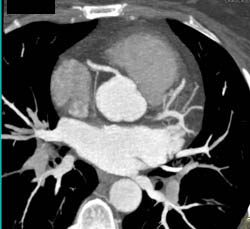

Diagnosis

Normal Circumflex